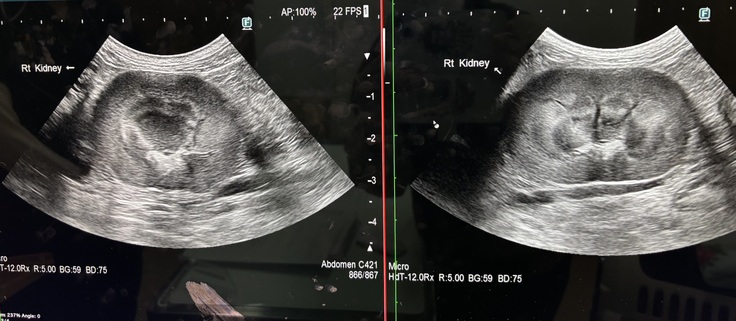

5月12日定期診察を受けてきました。

5月12日に骨盤骨折の術後経過と腎臓のエコー検査、血液検査を受けてきました。

骨折の方は順調に回復しており、腎臓も片腎ながら機能している右の腎臓には今のところ大きな問題はないとの診断をいただきました。